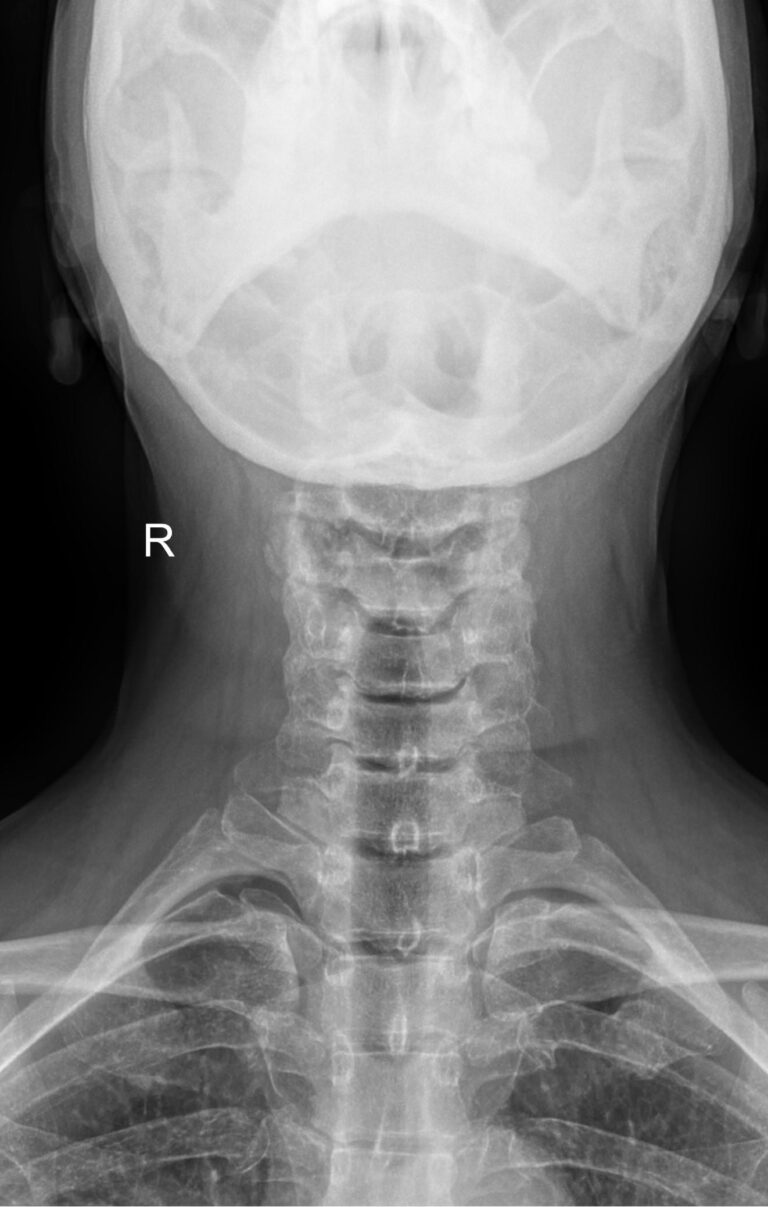

• Сохранение или сглаживание естественного лордоза в нейтральном положении, то есть на первом снимке;

• Смещение вперед или назад каждого позвонка по отношению к нижележащим при сгибании и разгибании;

• Деформацию передней стенки позвоночного канала из-за смещения позвонков;

• Сужения, расширения или отсутствие изменений межпозвоночных пространств;

• Изменения формы тел позвонков, наличие остеофитов;

• Аномалии развития.